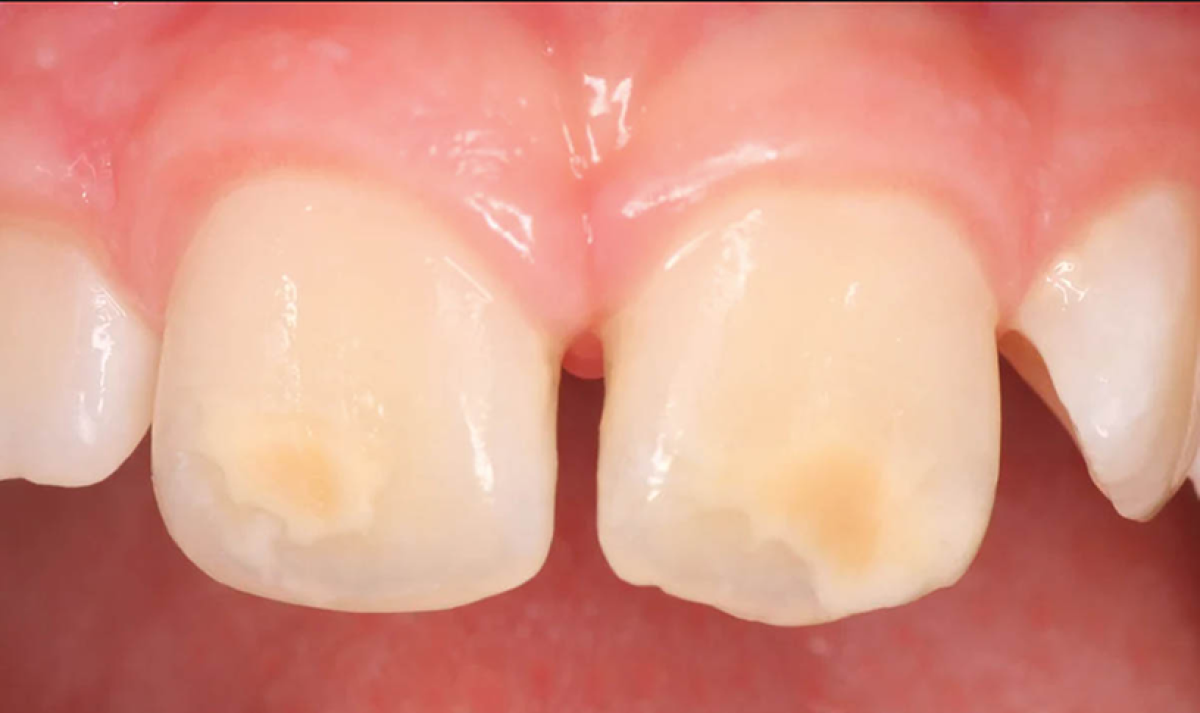

Molto frequentemente le mamme si preoccupano notando, sulla superficie dei denti dei loro bambini, irregolarità più o meno evidenti e/o macchie scure o chiare, dovute ad un fenomeno definito amelogenesi imperfetta dello smalto. La dottoressa Beccuti del Centro Facekids ci spiega di cosa si tratta e come si cura.

«È un difetto dello smalto geneticamente determinato che può manifestarsi in maniera diversa clinicamente, istologicamente, geneticamente e per numero di elementi coinvolti. Può presentare mancanze sia qualitative sia quantitative dal punto di vista della mineralizzazione e maturazione dello smalto.»

Nell’amelogenesi imperfetta si distinguono:

• TIPO IPOPLASTICO: aspetto puntiforme, liscio o rugoso, con smalto molto sottile

• TIPO IPOCALCIFICATO: smalto facilmente perforabile con le sonde

• TIPO IPOMATURATIVO: pigmentato o bianco con smalto morbido e friabile